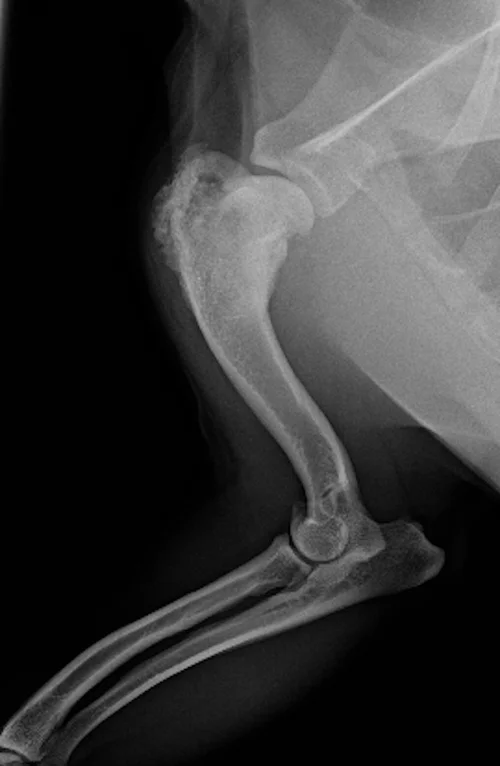

Dogs who have an amputation followed by chemotherapy may live up to. The most common type of primary bone tumor that arises in dogs is osteosarcoma OSA. The exact causes of dog cancer are still unclear although as mentioned above all forms of cancer start by genetic mutations that convert normal cells into cancer cells.

The final stages of osteosarcoma in dogs are characterized by spread to secondary tumors mostly localized to the lungs. Osteosarcoma OSA At the top of the list Osteosarcoma is the most prevalent type of bone cancer in dogs. The most common type of primary bone tumor that arises in dogs is osteosarcoma OSA.

Cancer will kill you if the cancer cells invade healthy tissue organs and impair their function. Sometimes bone cancer makes a sudden appearance as a lump in the leg or in worst case scenario as a pathologic fracture. But in most dogs bone cancer shows up slowly often over a few months.

If your dog has bone cancer you will also need to make changes in his diet. Types of Bone Cancer in Dogs 1. With bone cancer this can occur by affecting blood cell production in the bone or the cancer can metastasize to other organs and cause organ failiure.